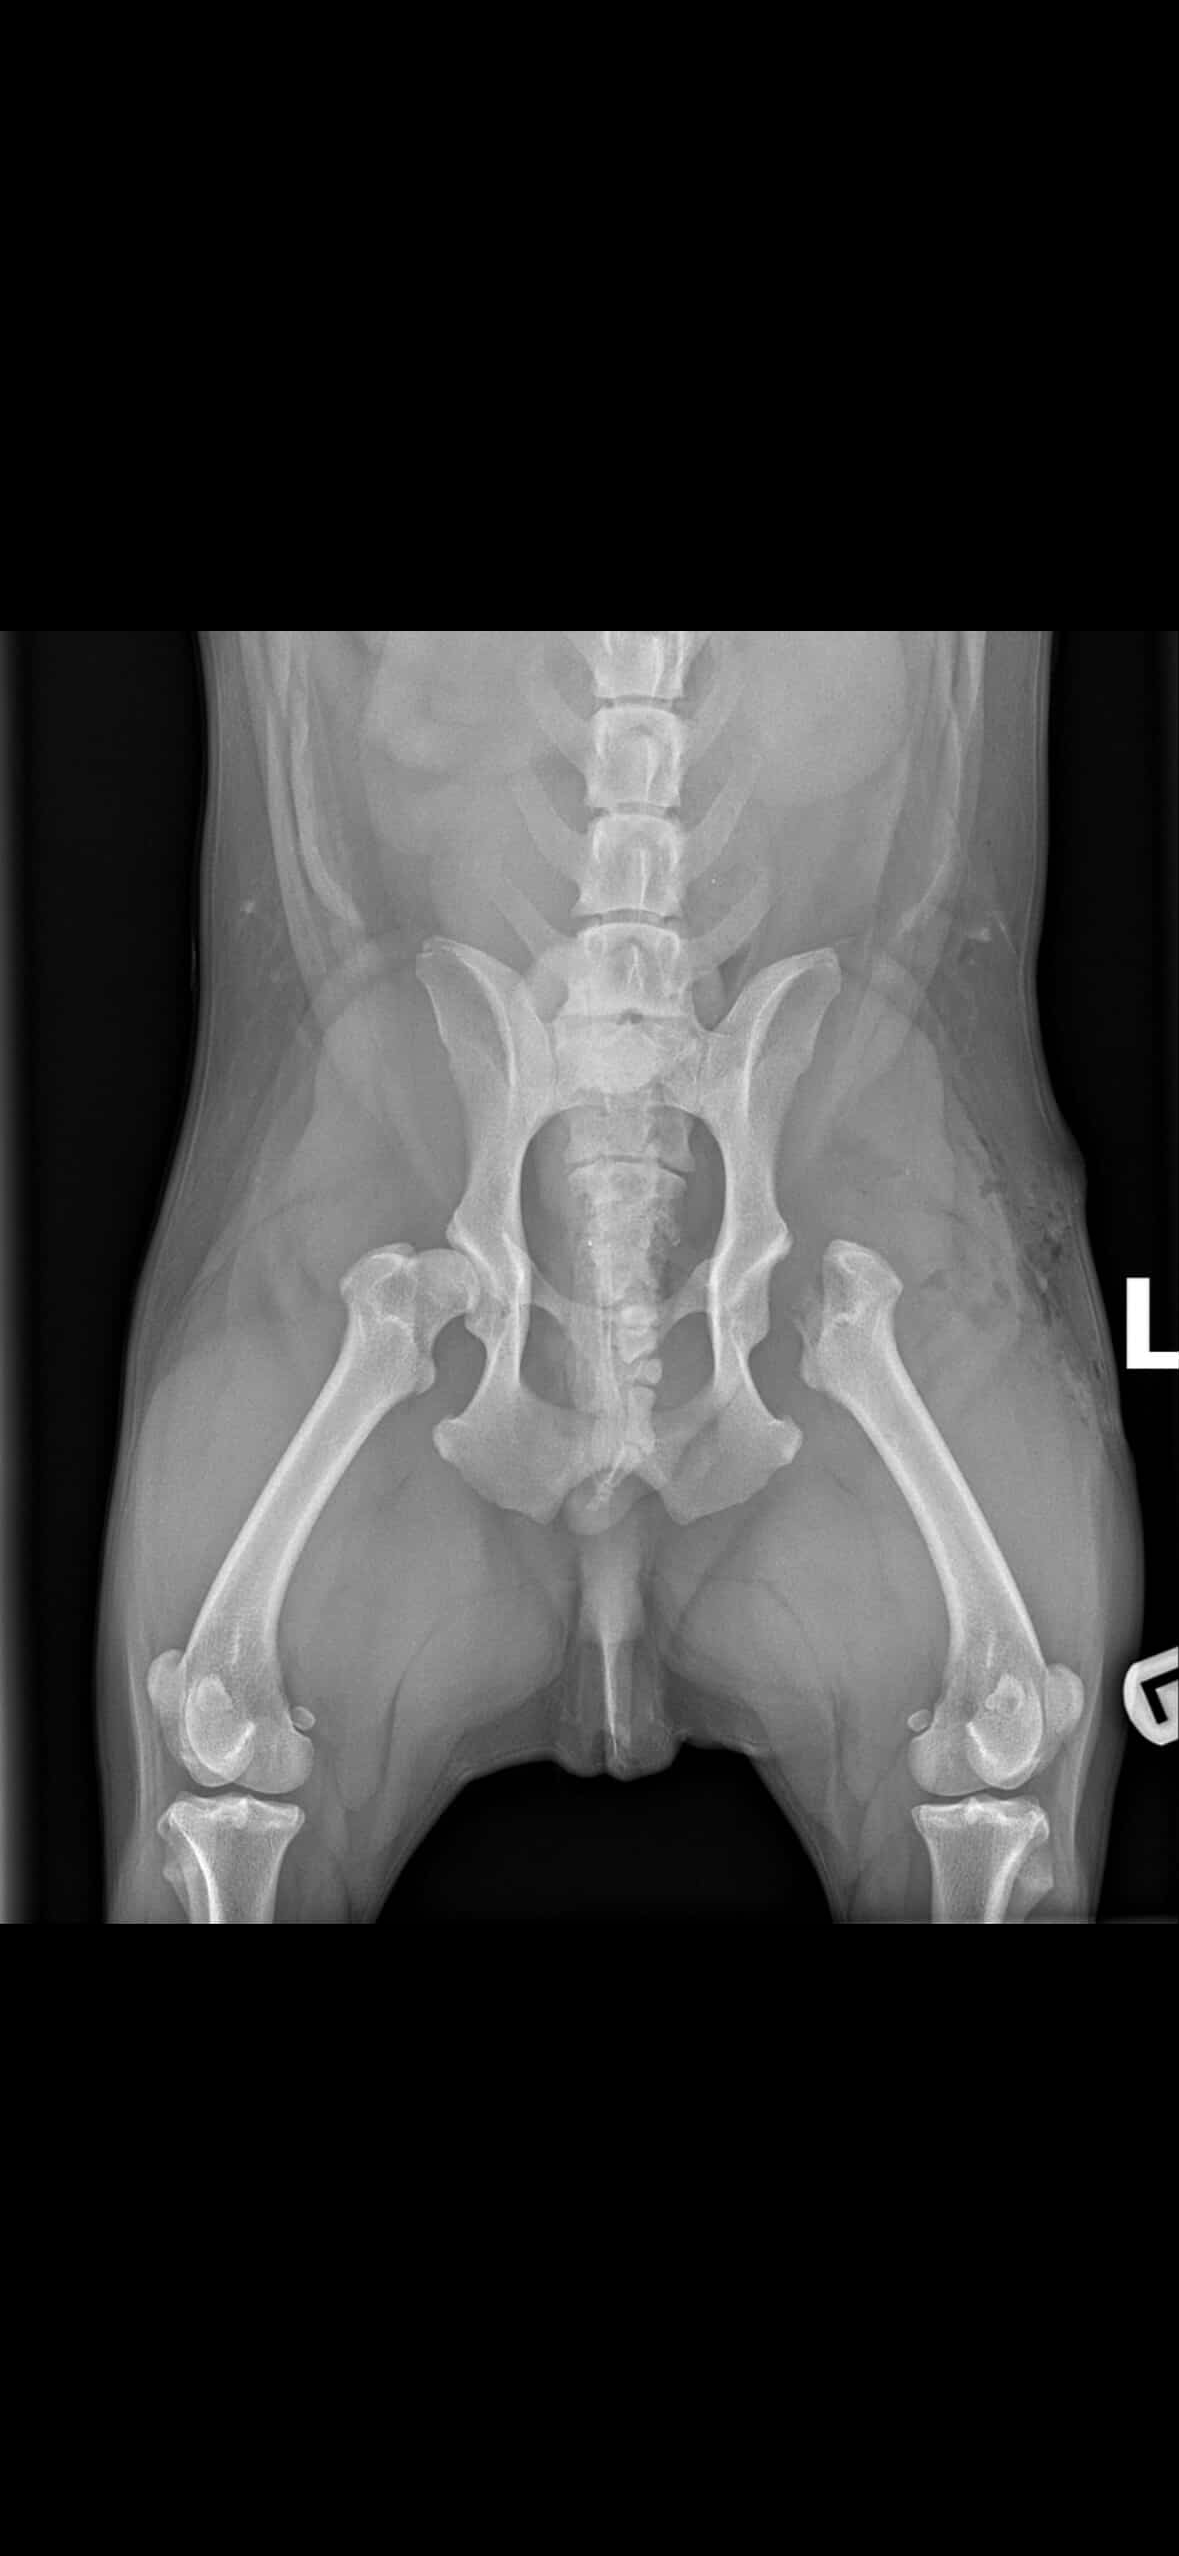

Hi my name is Lexi. I am attempting to help a friend in need. Someone who does so much for others and never asks anything in return. Her baby Dom, a 5 year old French bull dog needs your help. He was diagnosed with hip dysplasia and has completed one of the two surgeries required for him to walk properly and without pain. Maddy is attempting to pay for these out of pocket. Let’s gather around our friend in need and show the support she has always given to others. Anything helps and is very much appreciated!